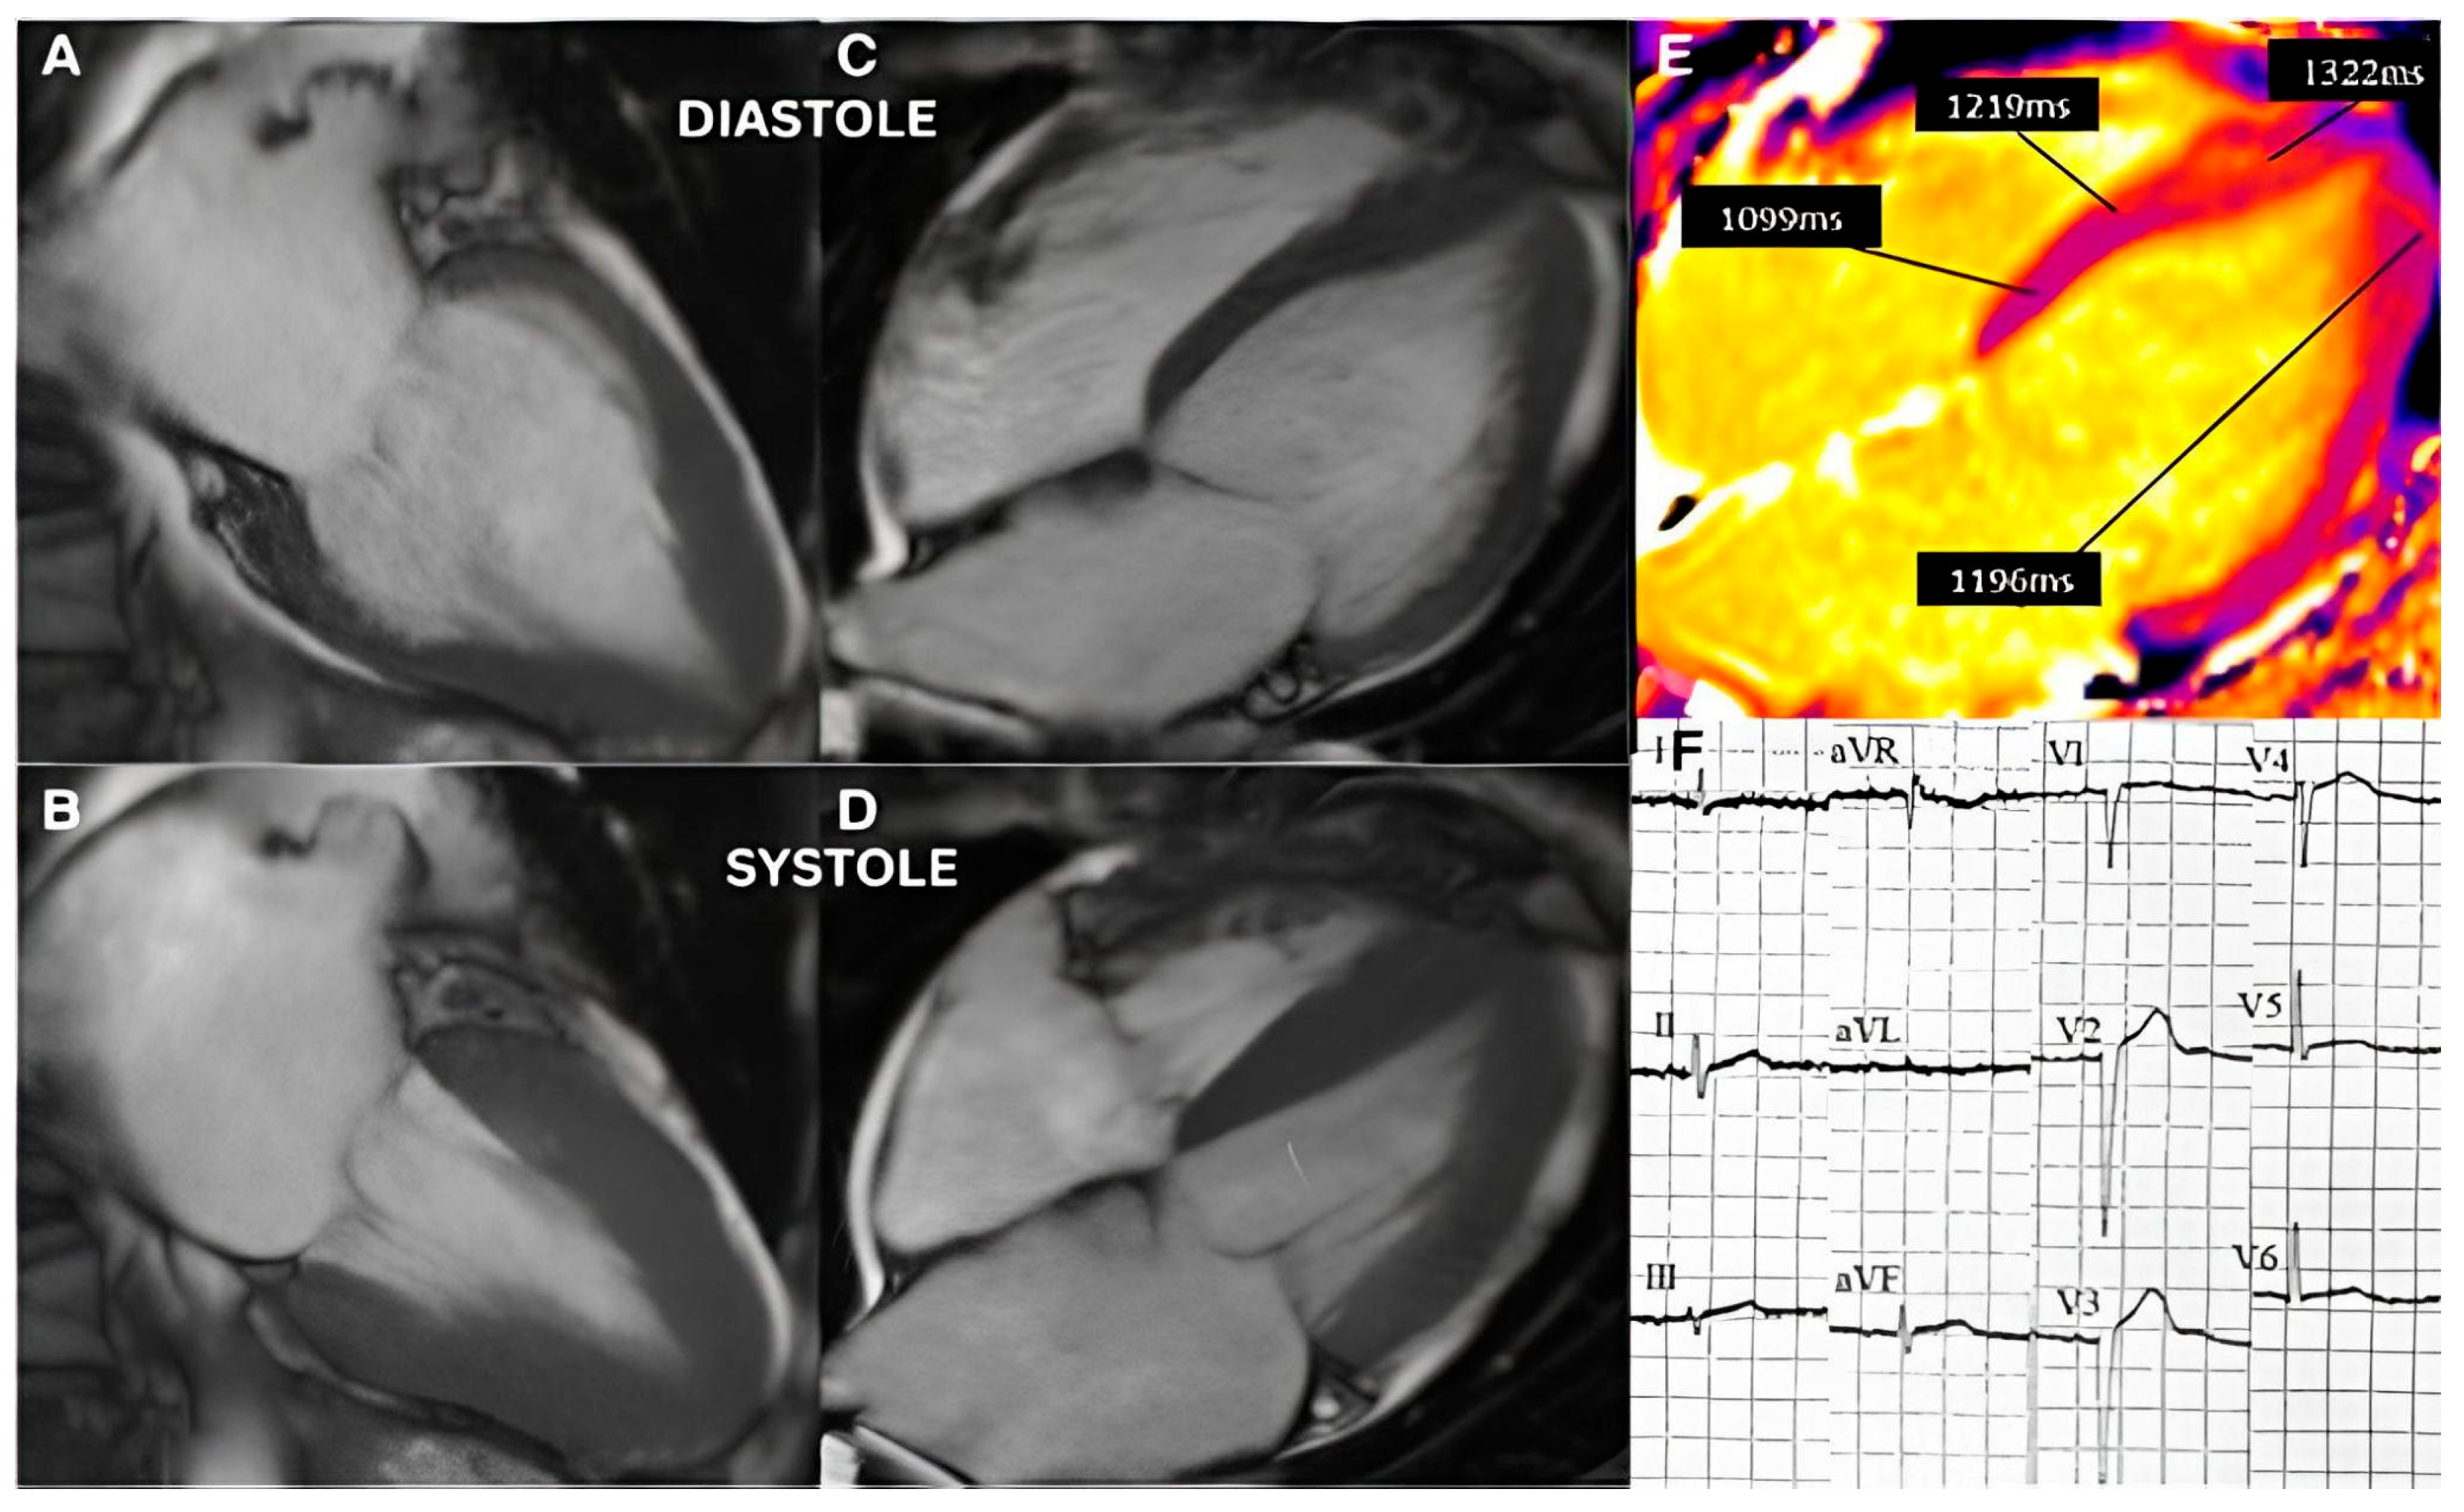

3.2. Imaging and Hemodynamic Observations

- Çağatay, B.; Yalçin, F.; Kıraç, A.; Küçükler, N.; Abraham, M.R. The Science Behind Stress: From Theory to Clinic, Is Basal Septal Hypertrophy the Missing Link between Hypertension and Takotsubo Cardiomyopathy? Stresses 2024, 4, 330–341. [Google Scholar] [CrossRef]

- Seyani, C.; Adam, R.; Gant, D.; Shambrook, J.; Flett, A. A Dynamic Variant of Takotsubo Cardiomyopathy Mimicking Apical Hypertrophic Cardiomyopathy: A Case Report. Eur. Heart J. Case Rep. 2025, 9, ytae432. [Google Scholar] [CrossRef] [PubMed]

- Yalçin, F.; Çağatay, B.; Küçükler, N.; Abraham, T.P. Geomeric and Functional Aspects in Hypertension and Takotsubo: Importance of Basal Septal Hypertrophy. Eur. J. Prev. Cardiol. 2023, 30, 1996–1997. [Google Scholar] [CrossRef]

- Merli, E.; Sutcliffe, S.; Gori, M.; Sutherland, G. Tako-Tsubo Cardiomyopathy: New Insights into the Possible Underlying Pathophysiology. Eur. J. Echocardiogr. 2006, 7, 53–61. [Google Scholar] [CrossRef]

- Yalçin, F.; Muderrisoǧlu, H. Tako-Tsubo Cardiomyopathy May Be Associated with Cardiac Geometric Features as Observed in Hypertensive Heart Disease. Int. J. Cardiol. 2009, 135, 251–252. [Google Scholar] [CrossRef]